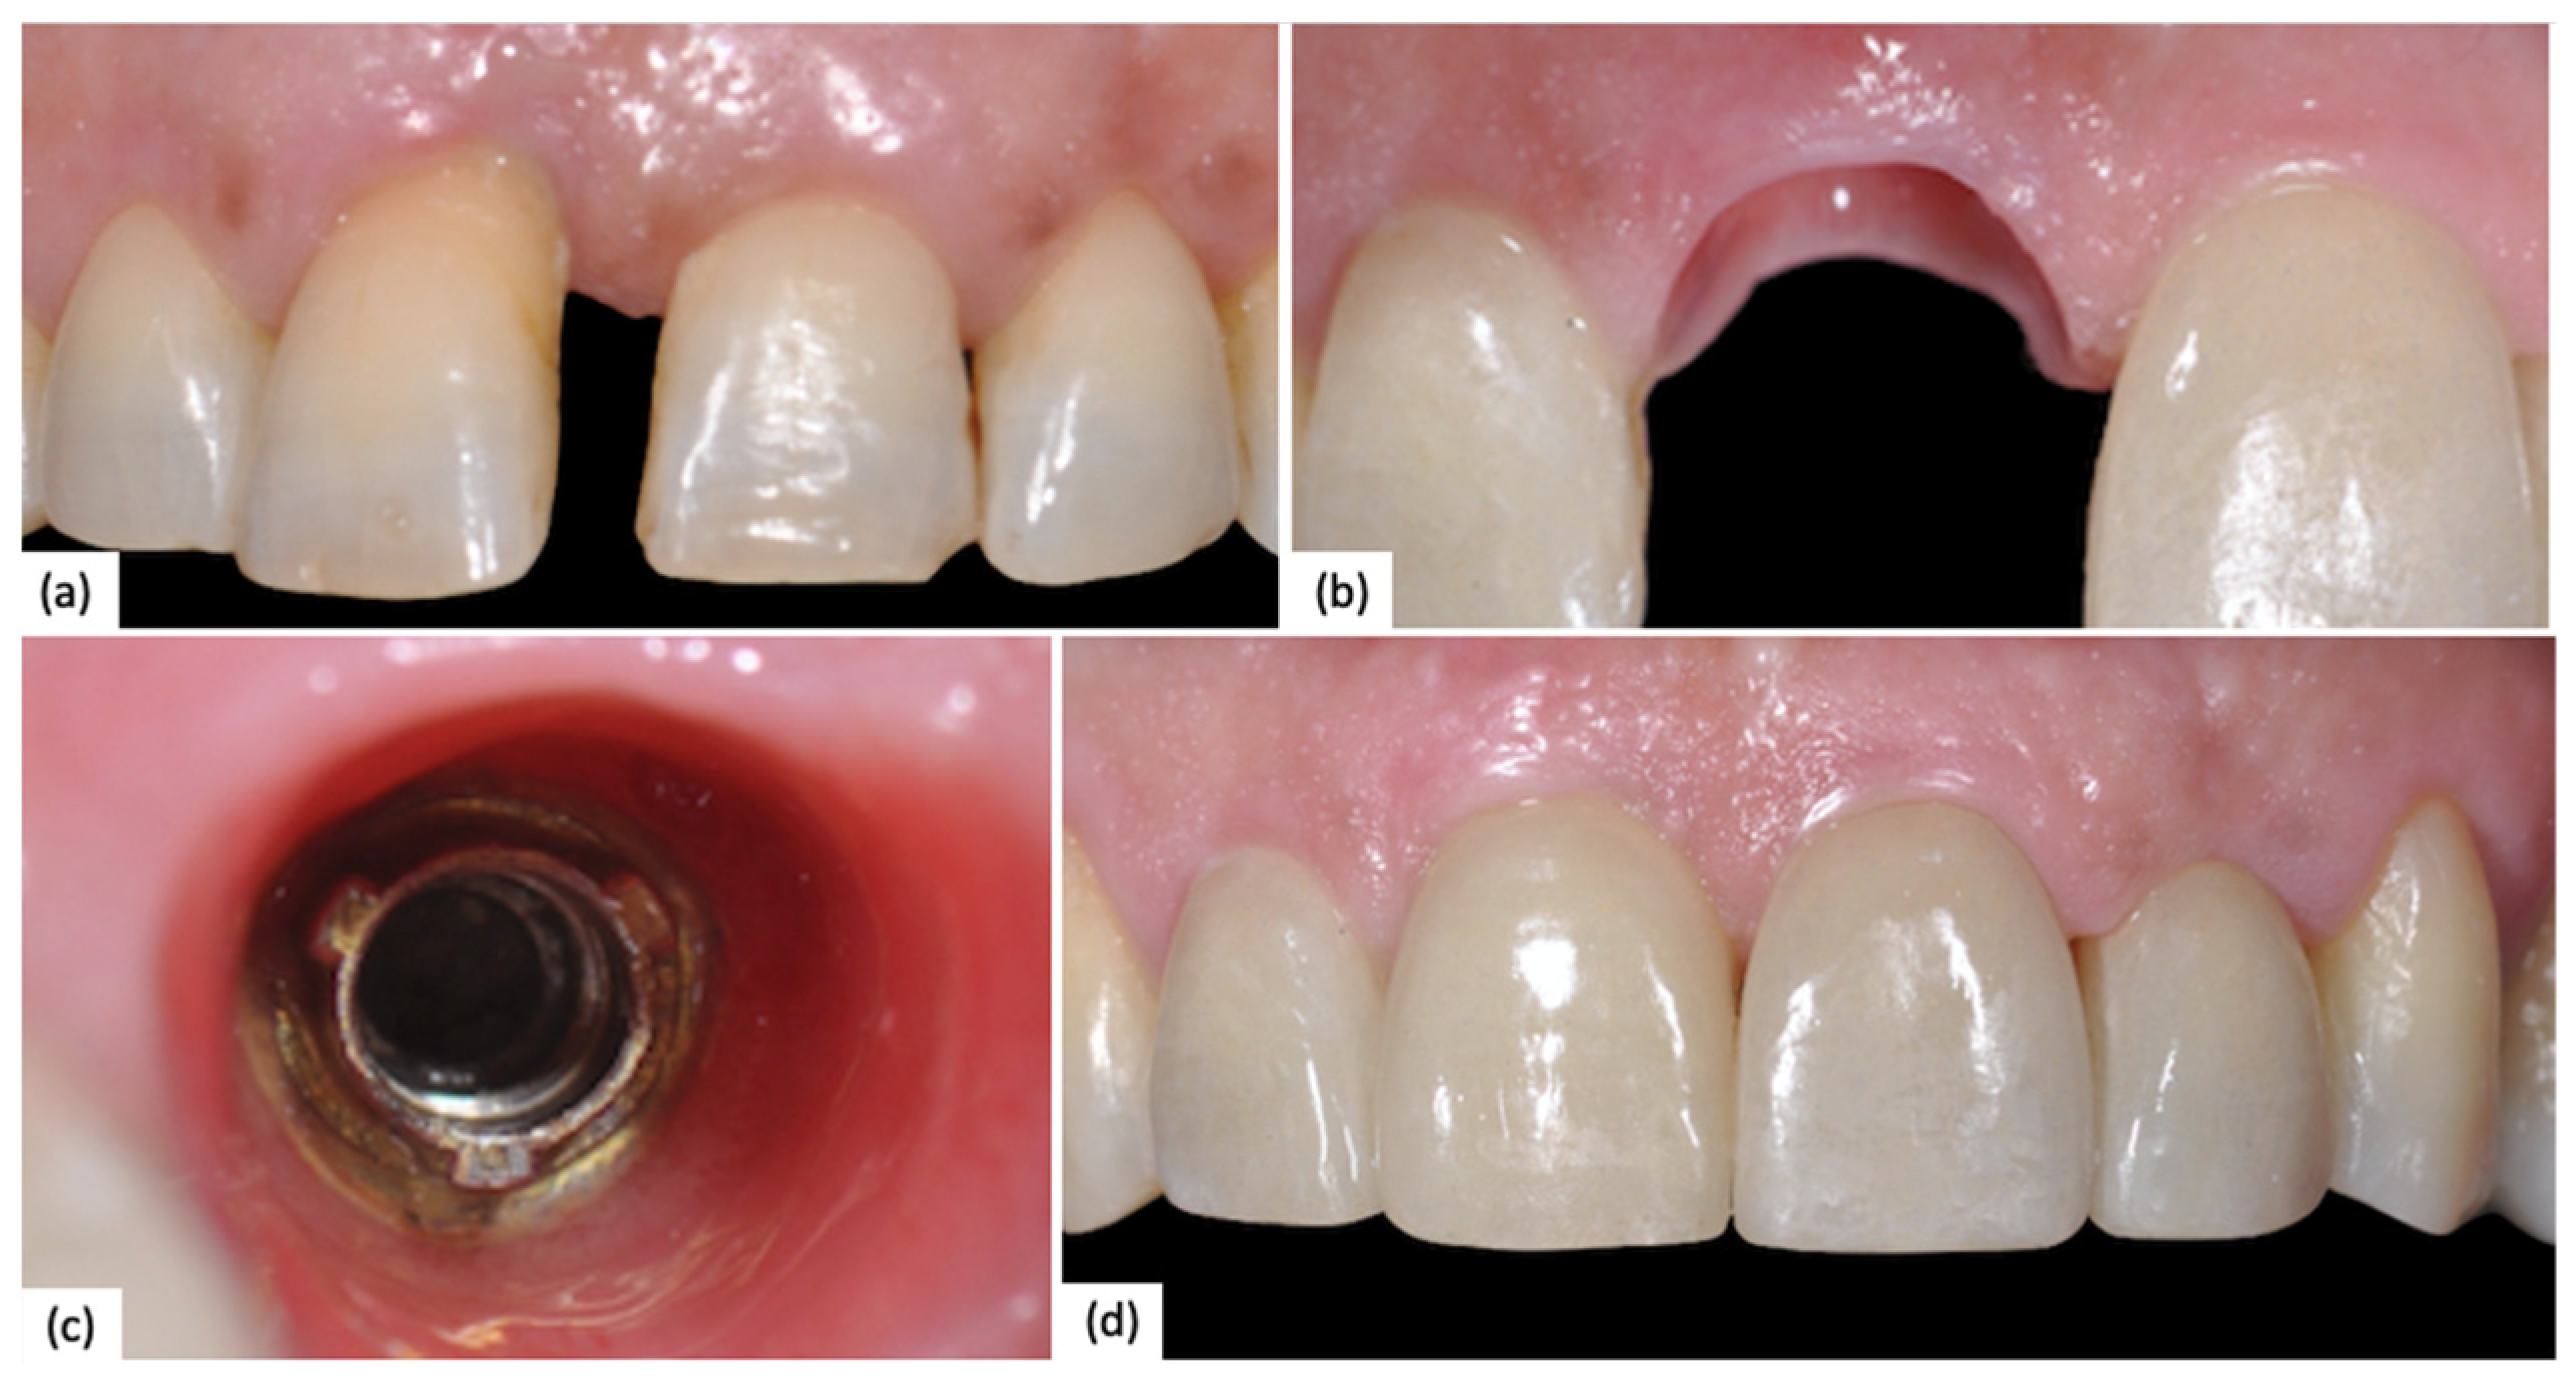

A clinical case of a 2.5 (NobelReplace) with fully digital workflow is reported below (Figure 1).

Figure 1. (a) Occlusal contact check; (b) Intraoral Rx confirms a correct implant–abutment fit; (c) Interproximal contact check; (d) Digital planning of implant insertion. The yellow line represents the expected maxillary sinus lift.